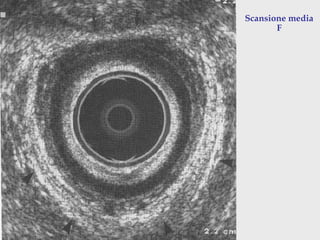

A: tessuto subepiteliale

B : sfintere anale interno

C: muscolo longitudinale

D : sfintere esterno

Scansione media

F